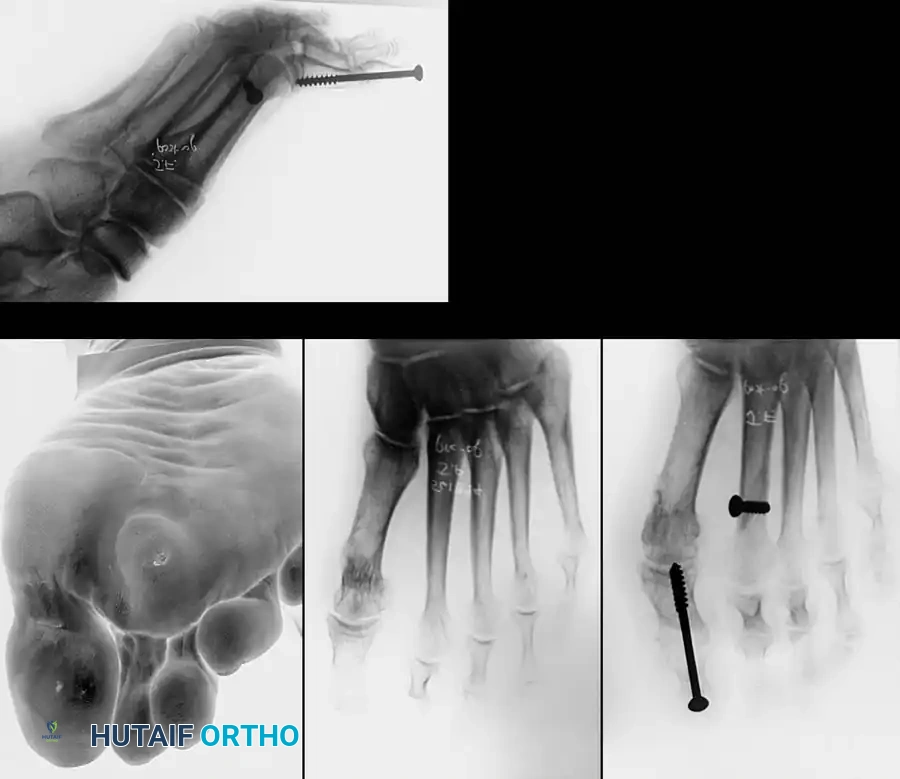

Combined Hammer and Mallet Toe Deformity with Double Corns: Surgical Management

PATHOMECHANICS OF COMBINED HAMMER TOE AND MALLET TOE DEFORMITY

The combined hammer toe and mallet toe deformity, frequently presenting with associated double corns, represents a distinct biomechanical entity in forefoot pathology. It differs fundamentally from the traditional claw toe deformity in that there is minimal to no extension deformity at the metatarsophalangeal (MTP) joint. Instead, the primary deforming forces are concentrated distally, resulting in rigid flexion contractures at both the proximal interphalangeal (PIP) and distal interphalangeal (DIP) joints.

Because of this dual-level contracture, the toe is subjected to abnormal shear and compressive forces within the shoe. Large, prominent hyperkeratotic lesions—double corns—typically develop over the dorsal aspects of both the PIP and DIP joints. The management of these lesions requires a deep understanding of the underlying osseous prominences. In a retrospective review of combined DIP and PIP resection arthroplasties, Oliver et al. reported a 10% recurrence rate at the PIP joint, which they attributed directly to inadequate bone resection during the index procedure.

COMBINED HAMMER TOE AND MALLET TOE DEFORMITY WITH ASSOCIATED DOUBLE CORNS Surgical Diagram